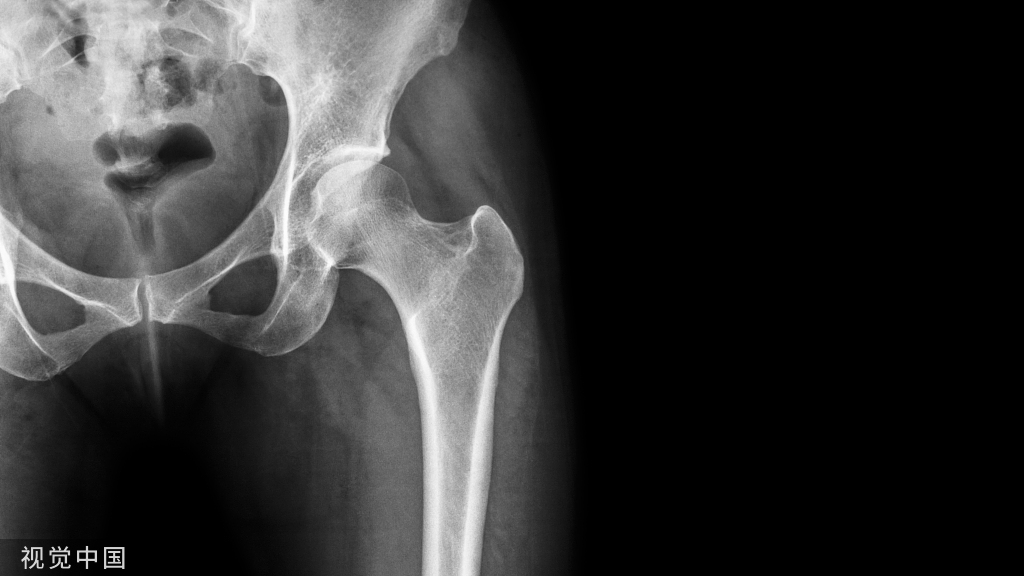

病例报告。19岁男性,脊柱侧凸手术,T2-L1固定,置钉过程SEP正常,矫形上第二根棒时波幅下降90%,唤醒下肢不能活动。减少矫形度数后波幅没有完全恢复,术后病人没有神经症状。6月后病人逐渐出现痉挛性瘫痪表现,下肢肌力4级,肌张力增高,病理征阳性。CT和MRI显示左侧T5椎弓根钉进入椎管。翻修手术取出左侧T5钉子,3月后脊髓症状消失。